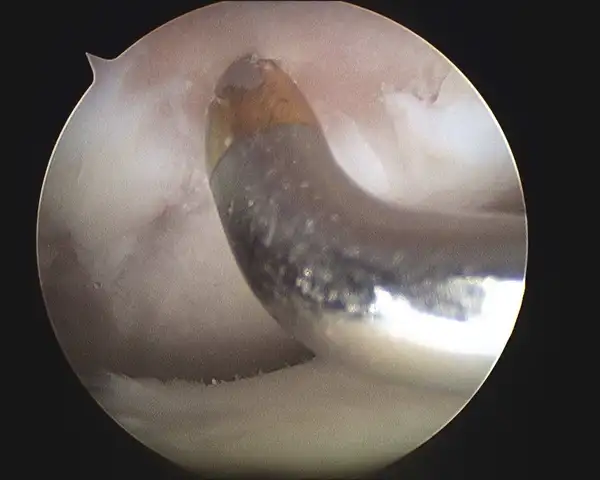

Series of Tibia OCD Microfracture

Pic during microfracture of tibial OCD.